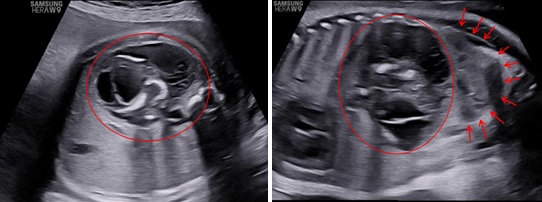

Siêu âm ngã bụng với máy HERA W9 (Samsung) ở các thời điểm 31 tuần 4 ngày, 34 tuần 3 ngày và 39 tuần. Ở hạ sườn trái và cực trên của thận trái có một khối không đồng nhất với kích thước tăng theo tuổi thai lần lượt là: 45x50x42mm, 48x58x50mm và 80x74x66mm. Bên trong khối này thấy hình ảnh vôi hoá có dạng của xương vòm sọ, xương đùi, xương sống và hình ảnh các cấu trúc này rõ khi tuổi thai lớn hơn. Trên Doppler màu, có một mạch máu nuôi khối này xuất phát từ động mạch chủ bụng của thai vật chủ với dạng sóng của động mạch rốn.

Hình 4: Siêu âm Doppler màu cho thấy khối này có một mạch máu nuôi xuất phát từ động mạch chủ và trên Doppler xung có phổ của động mạch rốn.